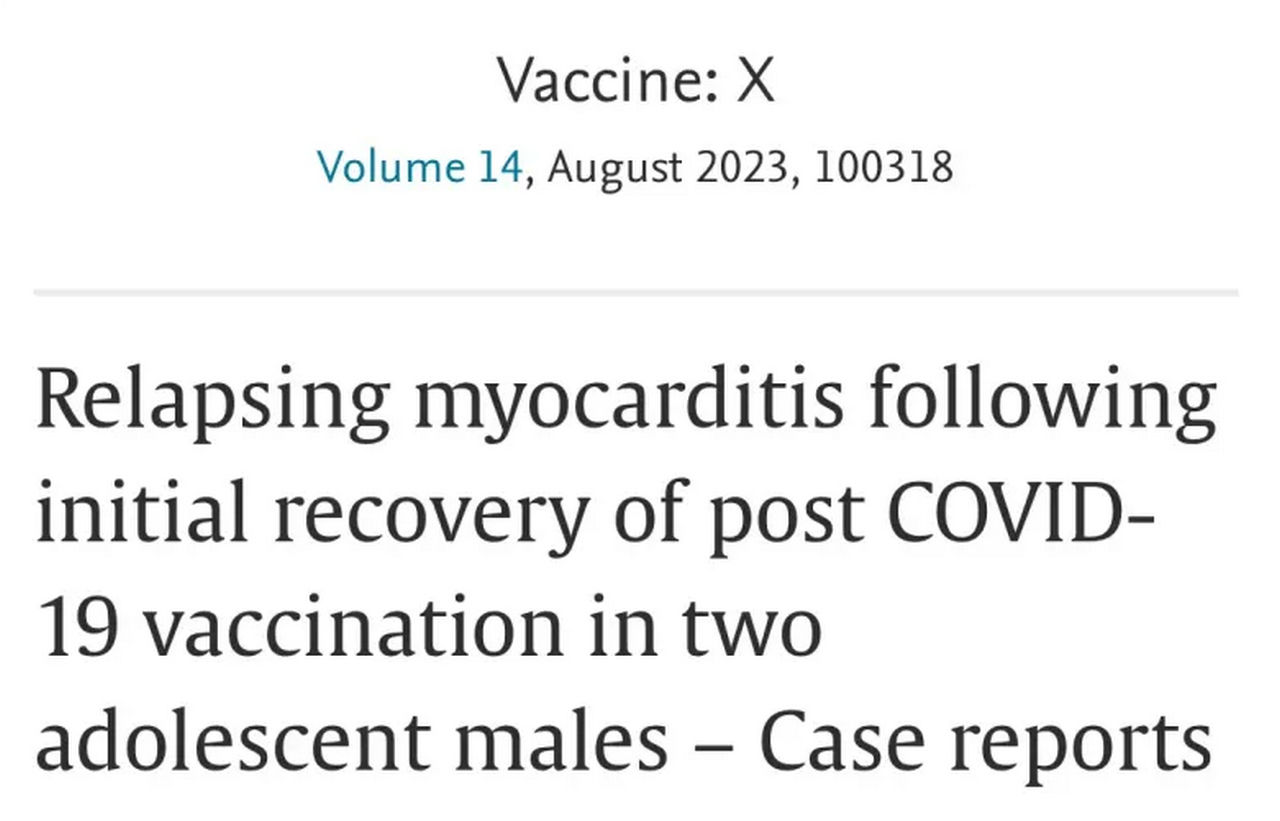

| Italian Researchers Find that Teenage Boys | Italienische Forscher stellen bei Jungen im Teenageralter |

| Relapse After Apparently Full Recovery | nach scheinbar vollständiger Genesung einen Rückfall |

| of Myocarditis Due to the Covid Vaccine | der Myokarditis durch den Covid-Impfstoff fest |

| uncut-news.ch, 9th August 2023, Alex Berenson | uncut-news.ch, August 9, 2023, Alex Berenson |

| The mRNA shots are the gift that keeps on giving. At best, we will be monitoring many adolescents and young adults for heart damage for a long, long time. | Die mRNA-Spritzen sind das Geschenk, das immer wieder gemacht wird. Im besten Fall werden wir viele Jugendliche und junge Erwachsene für eine lange, lange Zeit auf Herzschäden überwachen. |

| Two adolescents who developed heart muscle inflammation after being vaccinated with the Pfizer Covid vaccine and then appeared to recover suffered a relapse months later, Italian researchers report. | Zwei Jugendliche, die nach der Impfung mit dem Pfizer-Impfstoff Covid an einer Herzmuskelentzündung erkrankt waren und sich danach scheinbar erholt hatten, erlitten Monate später einen Rückfall, wie italienische Forscher berichten. |

| Both teenagers showed signs of new heart damage from the relapses, including high levels of proteins from damaged heart muscle. Computerised tomography scans showed new lesions in the heart wall of one boy, and he had to stay in hospital for almost two weeks. | Beide Teenager zeigten Anzeichen neuer Herzschäden durch die Rückfälle, einschliesslich hoher Konzentrationen von Proteinen aus geschädigtem Herzmuskel. Computertomografien zeigten bei einem Jungen neue Läsionen in der Herzwand, und er musste fast zwei Wochen im Krankenhaus bleiben. |

| The researchers were unable to determine why the boys suffered a relapse 8 to 12 months after the initial myocarditis. They called for closer monitoring of all persons diagnosed with mRNA-related myocarditis and more research to determine whether young human beings suffering from the disease could develop serious complications in the future. | Die Forscher konnten nicht feststellen, warum die Jungen 8 bis 12 Monate nach der ersten Herzmuskelentzündung einen Rückfall erlitten. Sie forderten eine strengere Überwachung aller Personen, bei denen eine mRNA-bedingte Herzmuskelentzündung diagnostiziert wurde, und mehr Forschung, um festzustellen, ob bei jungen Menschen, die an dieser Krankheit leiden, in Zukunft schwere Komplikationen auftreten könnten. |

| The case report published in the journal 'Vaccine: X' at the end of May appears to be the first to show that mRNA vaccines can cause recurrent myocarditis or inflammation of the heart. However, health authorities and the media, who have been downplaying the cardiac side effects of mRNA vaccines since 2021, have ignored this. | Der Ende Mai in der Fachzeitschrift ‹Vaccine: X› veröffentlichte Fallbericht scheint der erste zu sein, der zeigt, dass mRNA-Impfstoffe wiederkehrende Herzmuskelentzündungen oder Entzündungen des Herzens verursachen können. Die Gesundheitsbehörden und die Medien, die seit 2021 die kardialen Nebenwirkungen von mRNA-Impfstoffen herunterspielen, haben dies jedoch ignoriert. |

Recurrent myocarditis after initial recovery from COVID-19 vaccination in two male adolescents – case reports

Rezidivierende Myokarditis nach anfänglicher Erholung von der COVID-19-Impfung bei zwei männlichen Jugendlichen – Fallberichte